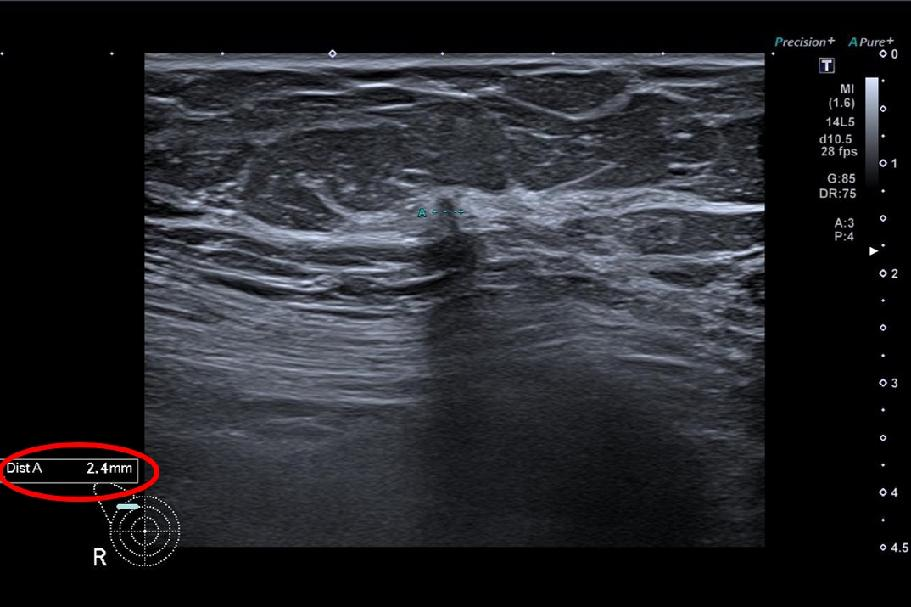

OZP je také první českou zdravotní pojišťovnou, která v preventivních programech využívá umělou inteligenci. Od 1. dubna 2023 plně hradí tzv. třetí čtení mamografických snímků. Odborným garantem tohoto projektu je prof. MUDr. Jan Daneš, CSc., předseda Komise pro screening karcinomu prsu. Podle něj se díky AI zvýšila citlivost screeningu až o 20 procent.

„Od ledna 2024 do srpna 2025 využilo možnost mamografického vyšetření s přispěním umělé inteligence 6397 našich klientek. Na základě nálezu pomocí AI absolvovalo 49 našich pojištěnek biopsii a u 34 z nich se potvrdil maligní nález. Využívání umělé inteligence nejen v rámci prevence tedy podle nás rozhodně dává smysl, zvyšuje celkovou senzitivitu vyšetření a snižuje počet zbytečných doplňujících vyšetření,“ komentuje dosavadní výsledky zdravotní ředitelka OZP MUDr. Jitka Vojtová, MBA.